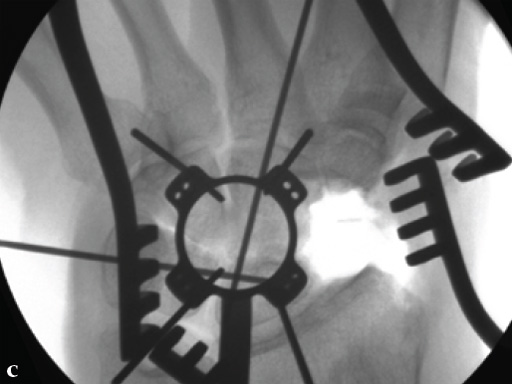

Fig 3ab Bone debridement. Guide positioning and fixation.

Fig 3c Bone debridement. Guide positioning and fixation.

Fig 4c Once the carpal junctions have been putting closer by the new reduction-compression guide, reaming is done.

Fig 5ab Plate positioning and fixation. The combined VA-locking-standard guide allows drilling in the appropriate direction.

Fig 5cd Plate positioning and fixation. The combined VA-locking-standard guide allows drilling in the appropriate direction.